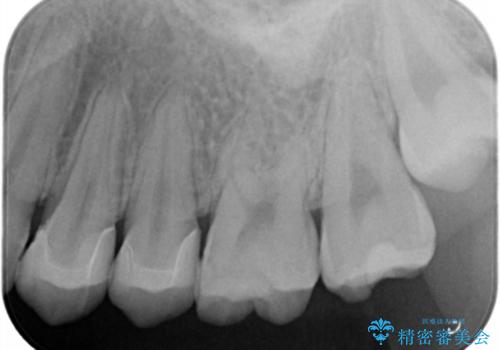

銀の詰め物を除去した後、う蝕が残っていないかを拡大鏡下で確認し

メタルインレーをそのままにしておくと、歯と詰め物の隙間から細菌が入り込み

虫歯の再発リスクが高まります。

セラミックの詰め物(e-maxインレー)は、歯と詰め物の隙間がなく

虫歯の再発リスクを下げる事ができます。